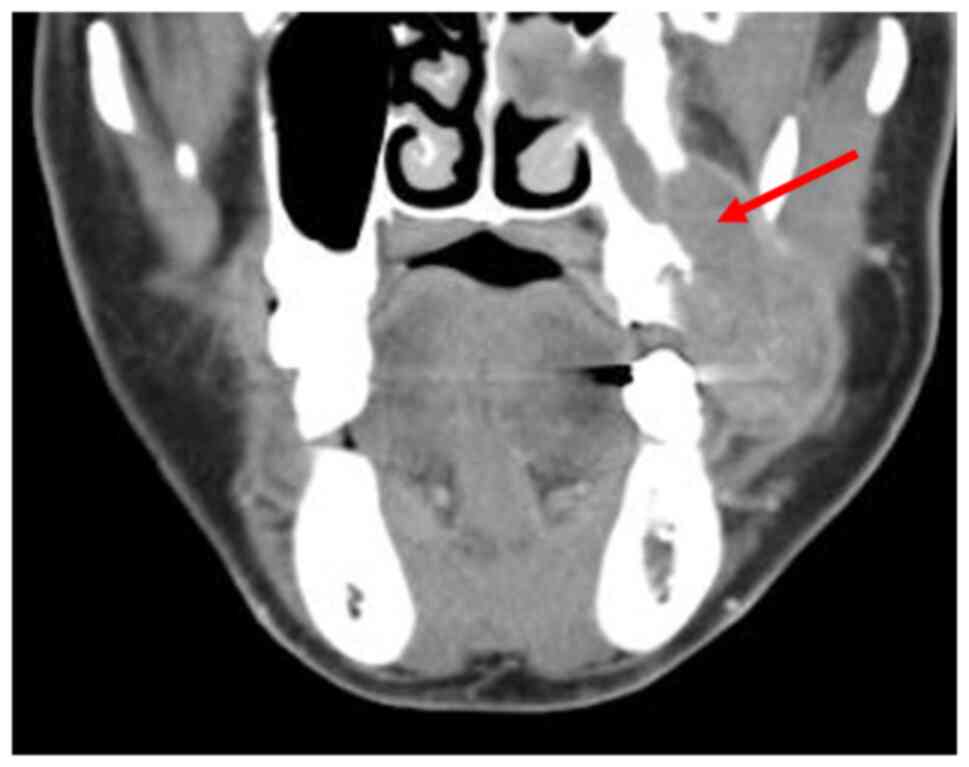

The patient underwent radiological, hematologic and histological examinations, with a differential diagnosis of a gingival tumor invading the maxillary sinus. Orthopantomography and computed tomography (CT) were performed in the radiology department. The orthopantomograms showed horizontal bone resorption in the jaw, particularly in the left maxillary molar root region and around the second premolar (Fig. 2). CT scan of the oral cavity showed a large, poorly demarcated soft tissue mass extending into the left maxillary sinus, with generalized bone resorption around the left second premolar and the base of the maxillary sinus (Fig. 3). CT scans of the chest and abdomen showed relatively distinct nodules in the lung and tumor recurrence in the residual bowel. Liver metastases were also detected. The hematology and blood biochemistry test results are shown in Table I. The levels of the tumor markers CEA and carbohydrate antigen 19-9 (CA19-9), also known as Sialyl-LewisA, were exponentially elevated; other blood parameters were essentially unremarkable.

Figure 3

Compute tomography image showing bone resorption around the maxillary tooth 6 on the left side of the maxillary sinus.